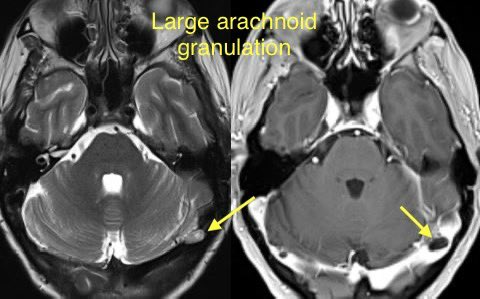

🔷TRANSVERSE SINUS STENOSIS & IDIOPATHIC INTRACRANIAL HYPERTENSION

🔸Intrinsic and extrinsic causes

INTRINSIC: Typically arachnoid granulations

🔹Arachnoid granulations may be incidental though they can produce IIH when obstructing a dominant transverse sinus or simultaneously blocking both

🔹Look for a round/lobulated filling defect with CSF signal on all images